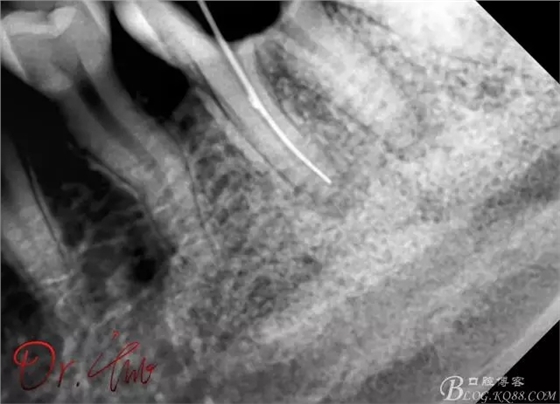

試主尖,近中頰側(cè)試主尖,此時手用銼02錐度的已擴到30號,可以明顯感覺到臺階位置,挫預(yù)彎后找好正確位置可順利到達根尖,但是機用銼就是下不去,也是郁悶

試主尖,在30號02錐度K挫到達根尖后,用02錐度牙膠尖找準(zhǔn)位置,進行試尖